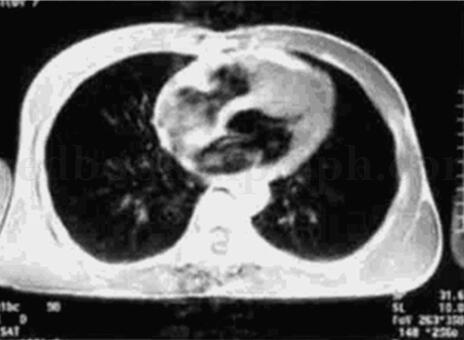

7﹒心脏MRI检查

在T1WI上可见室间隔心尖部明显肥厚。

(见图31‐24)

图31‐24 心脏MRI

4﹒MRI见室间隔心尖部明显肥厚;